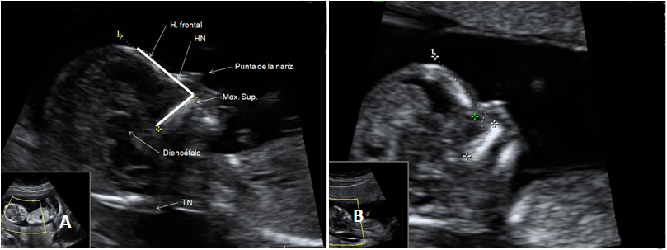

En la semana 12 de gestación, la embarazada aún no nota los movimientos del bebé que crece dentro de su útero. Pero en esta ecografía en 4D se observa sus vigorosos movimientos.

Ecografía 4D de feto de 12 semanas de espaldas

La curiosa ecografía de este feto de 12 semanas comienza con la imagen de espaldas. El niño se gira hasta colocarse de perfil y es entonces cuando empieza a mover brazos y piernas con agilidad. Todo un signo de bienestar fetal.